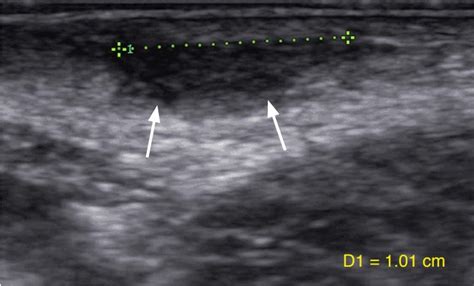

Showing posts matching the search for linear vulvar lesions